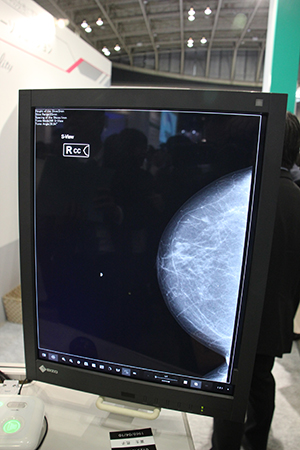

富士フイルムメディカルは,“Value from Innovation”のコーポレートスローガンのもと展示を展開した。富士フイルムは2014年に創立80周年を迎えるが,同社の中核事業のひとつであるメディカルシステム事業は,高い技術力をベースとしてさまざまな製品,ソリューションを提供することで臨床現場に価値を提供できることを強くアピールした。ブースは,中央にプレゼンテーションコーナーを設け,向かって右側がモダリティソリューション,左側がITソリューションで構成。モダリティコーナーでは,発表されたばかりの携帯型超音波画像診断装置「FUJIFILM FC1」を初出展。コンパクトなサイズの中に,同社の画像処理技術による高解像度と使いやすさをパッケージして,病院やクリニックでの幅広い検査に対応できることをアピールした。また,これもITEM直前にリリースされた同社のDRであるCALNEO Cシリーズの新画像処理ソフトウエア「Virtual Grid」を展示。画像処理によって散乱線成分を除去することでコントラストを向上しグリッドレスの撮影を可能にする。そのほか,マンモグラフィ「AMULET Innovality」や,トモシンセシス画像でトモ画像から2D画像を作成する“S-View”などの技術を紹介した。

トモシンセシスデータから2D画像を作成する